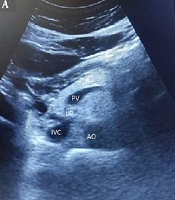

Ultrasound Findings of Liver and Pancreas in Children with Type 1 Diabetes Mellitus: A Case-Control Study

Maryam AlaeiORCID,

Farnaz Godazandeh,

Mahdieh Sadat Taghavi,

Milad Vakili Zarch,

Mohamad Ghazanfari HashemiORCID*

|

Final Published